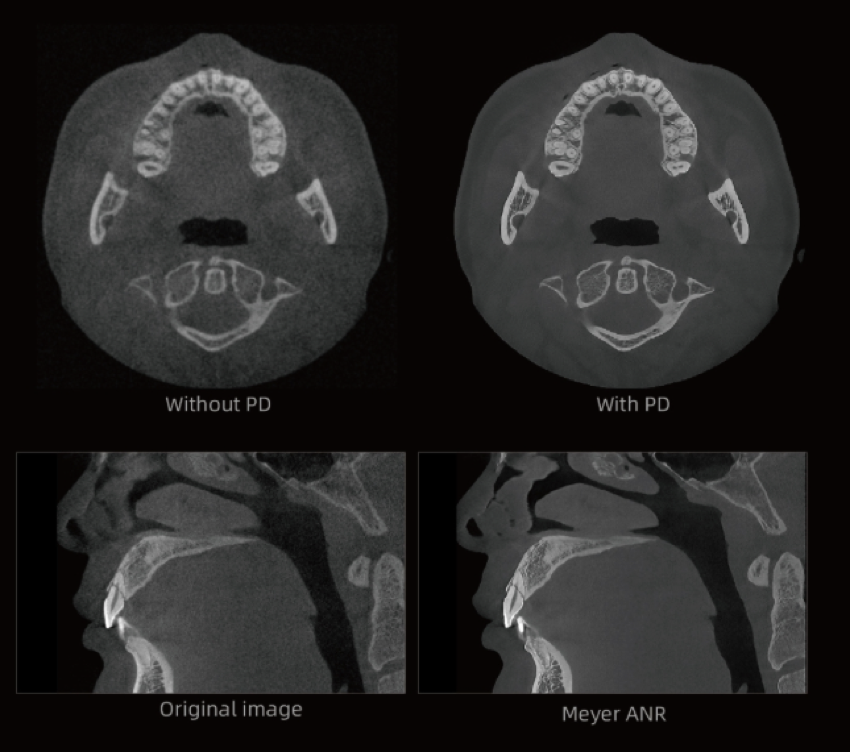

Algoritmo PD – Alta resolução espacial em TC até 2,8 lp/mm

Proporciona imagens com efeito de “textura natural”.

Previne eficazmente que pequenas lesões sejam ocultadas pela redução de ruído, reproduzindo com elevada fidelidade os detalhes do osso e dos tecidos moles.

Fornece aos clínicos informação diagnóstica mais precisa.

Algoritmo PD-MAR de Redução de Artefactos Metálicos

Tecnologia de correcção de artefactos líder na indústria, que elimina eficazmente artefactos persistentes em todos os cenários clínicos.

Restaura com precisão os detalhes estruturais dos tecidos.

Suporta Utilização Imediata e Comparação com Um Clique, melhorando significativamente a eficiência diagnóstica.